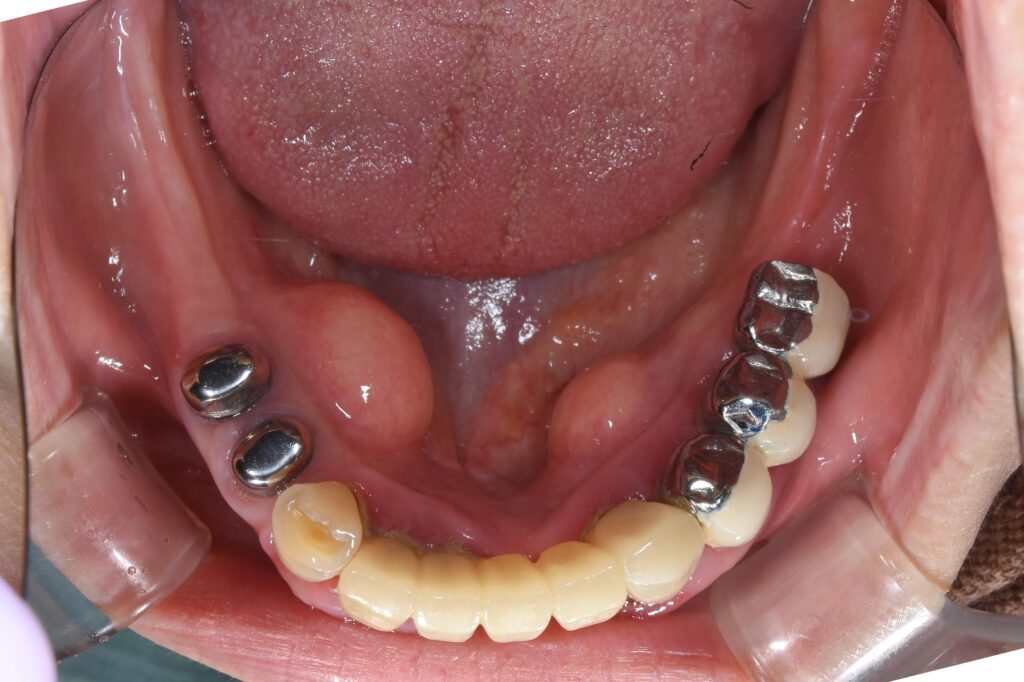

ここからどのような状態に変化していくのか、他の方の治療例で以下に示します。

【治療終了時の類似例】

いかがでしょうか。

この治療法のメリットは・・・

①取り外しの入れ歯なので入れ歯を外せば清潔に歯磨きができる

②多数のインプラントは必要ない。実際、今回治療をされている患者様は1本のインプラントのみ使用。

③硬いものも食べることが可能で、食事や会話の際に外れることはない。